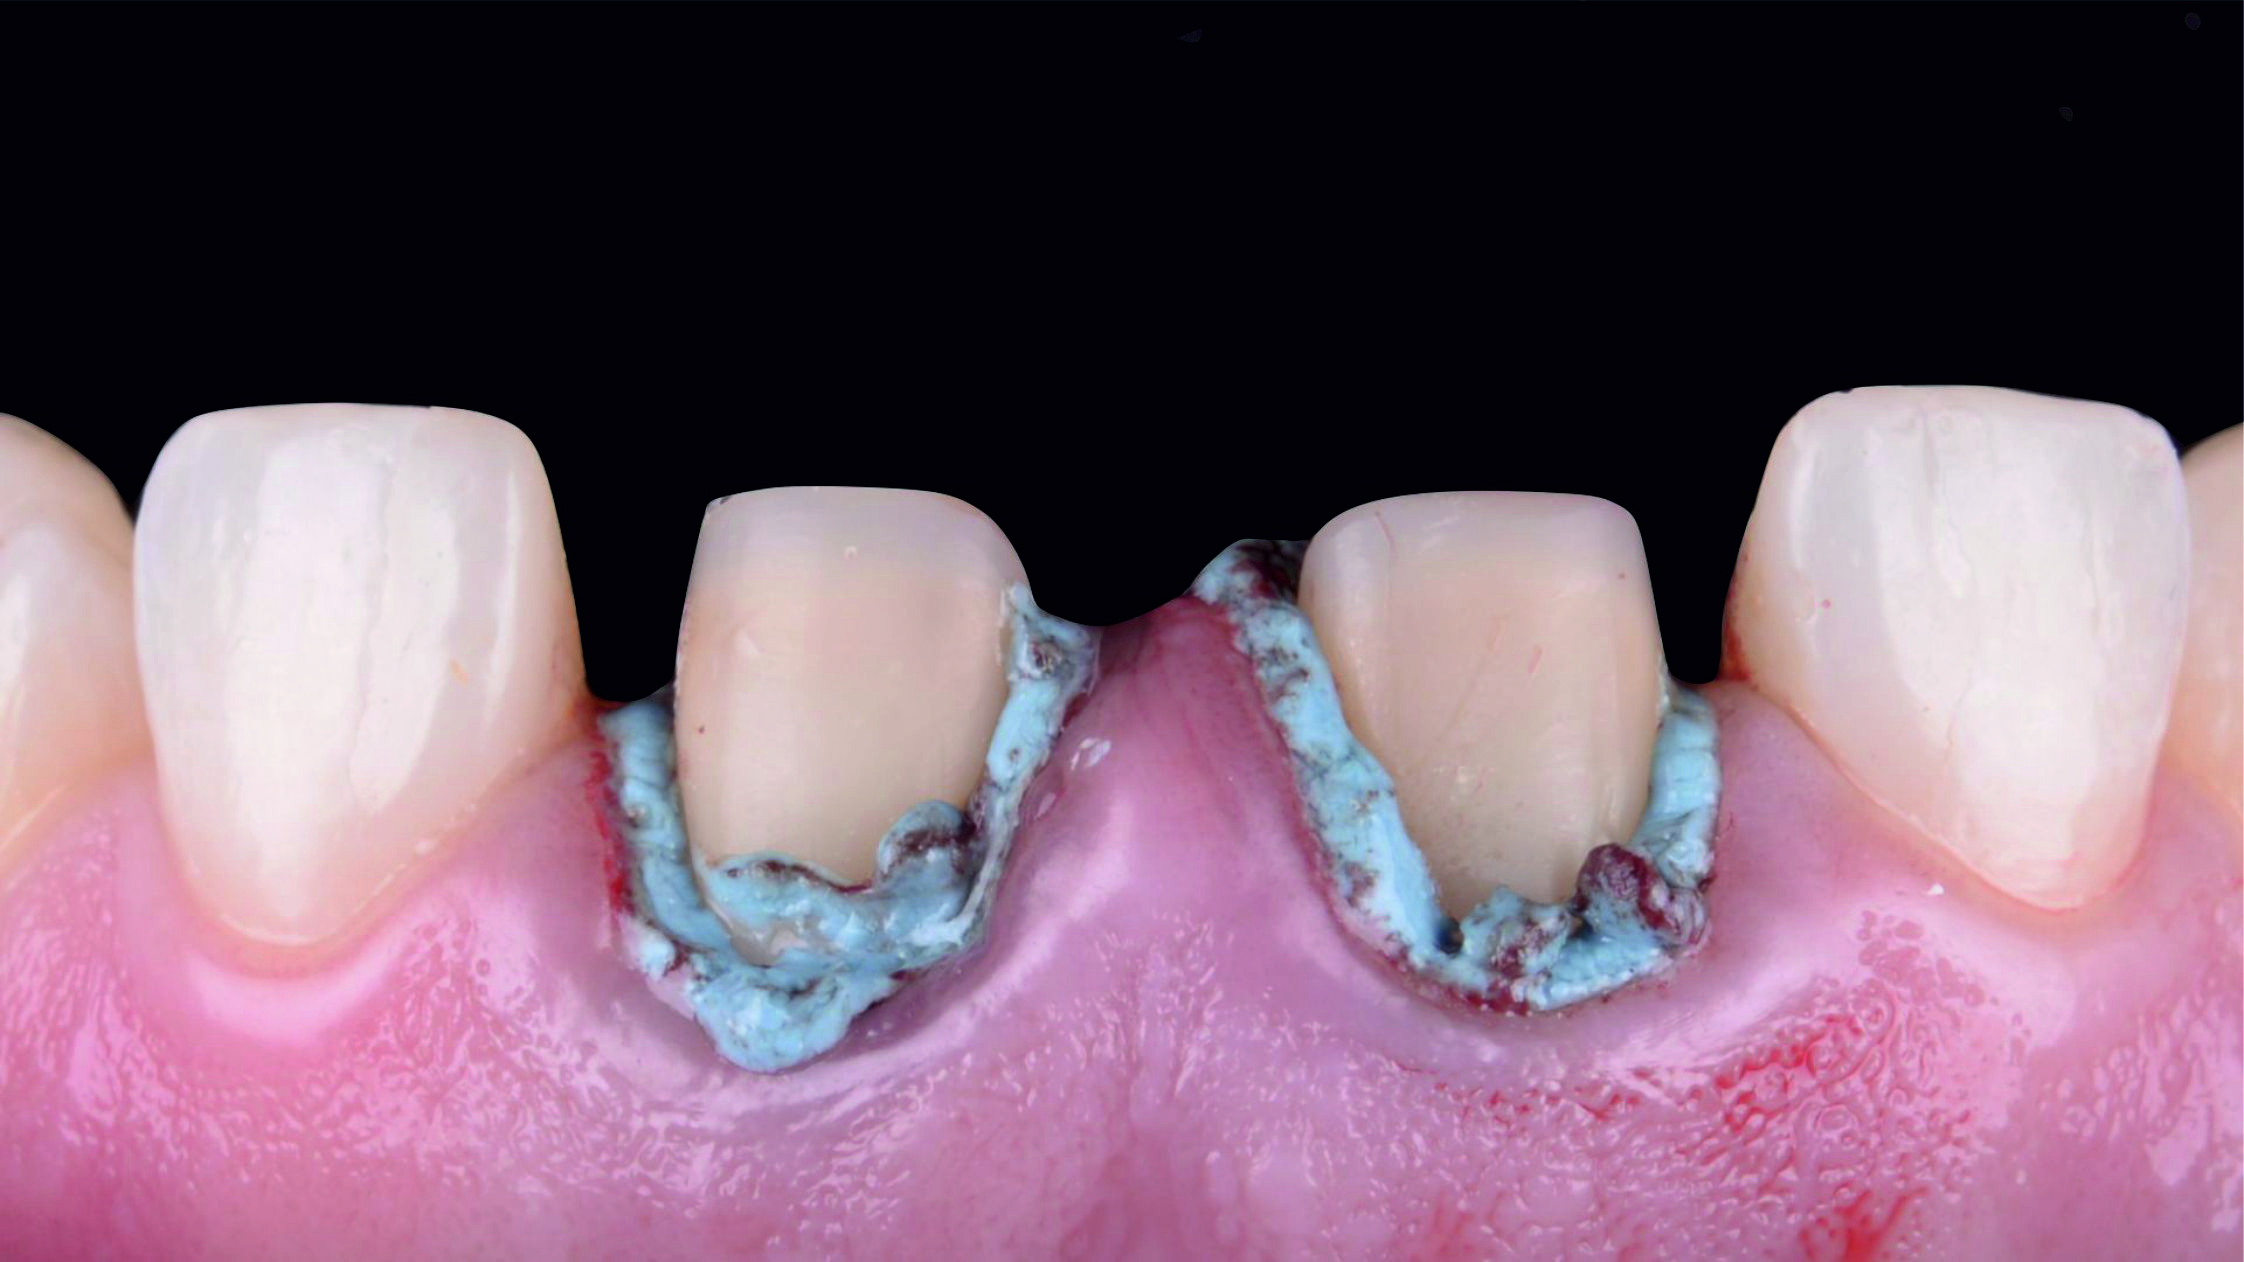

Фото 18. Після установки першої ретракційної нитки, просоченої хлоридом алюмінію, ми також виконали електрохірургічну підготовку і нанесли ретракційну пасту, сподіваючись отримати чіткі кордони препарування та добрий контроль виділення рідини.

Фото 19. Однак, незважаючи на всі наші старання, нам не вдалося забезпечити необхідні умови для отримання прогнозованого відбитка. У таких випадках, як цей, найкраще – це відкласти процедуру зняття відбитка, переробити або повторно виконати полірування тимчасових реставрацій та спробувати створити оптимальні умови для загоєння тканин пародонта.